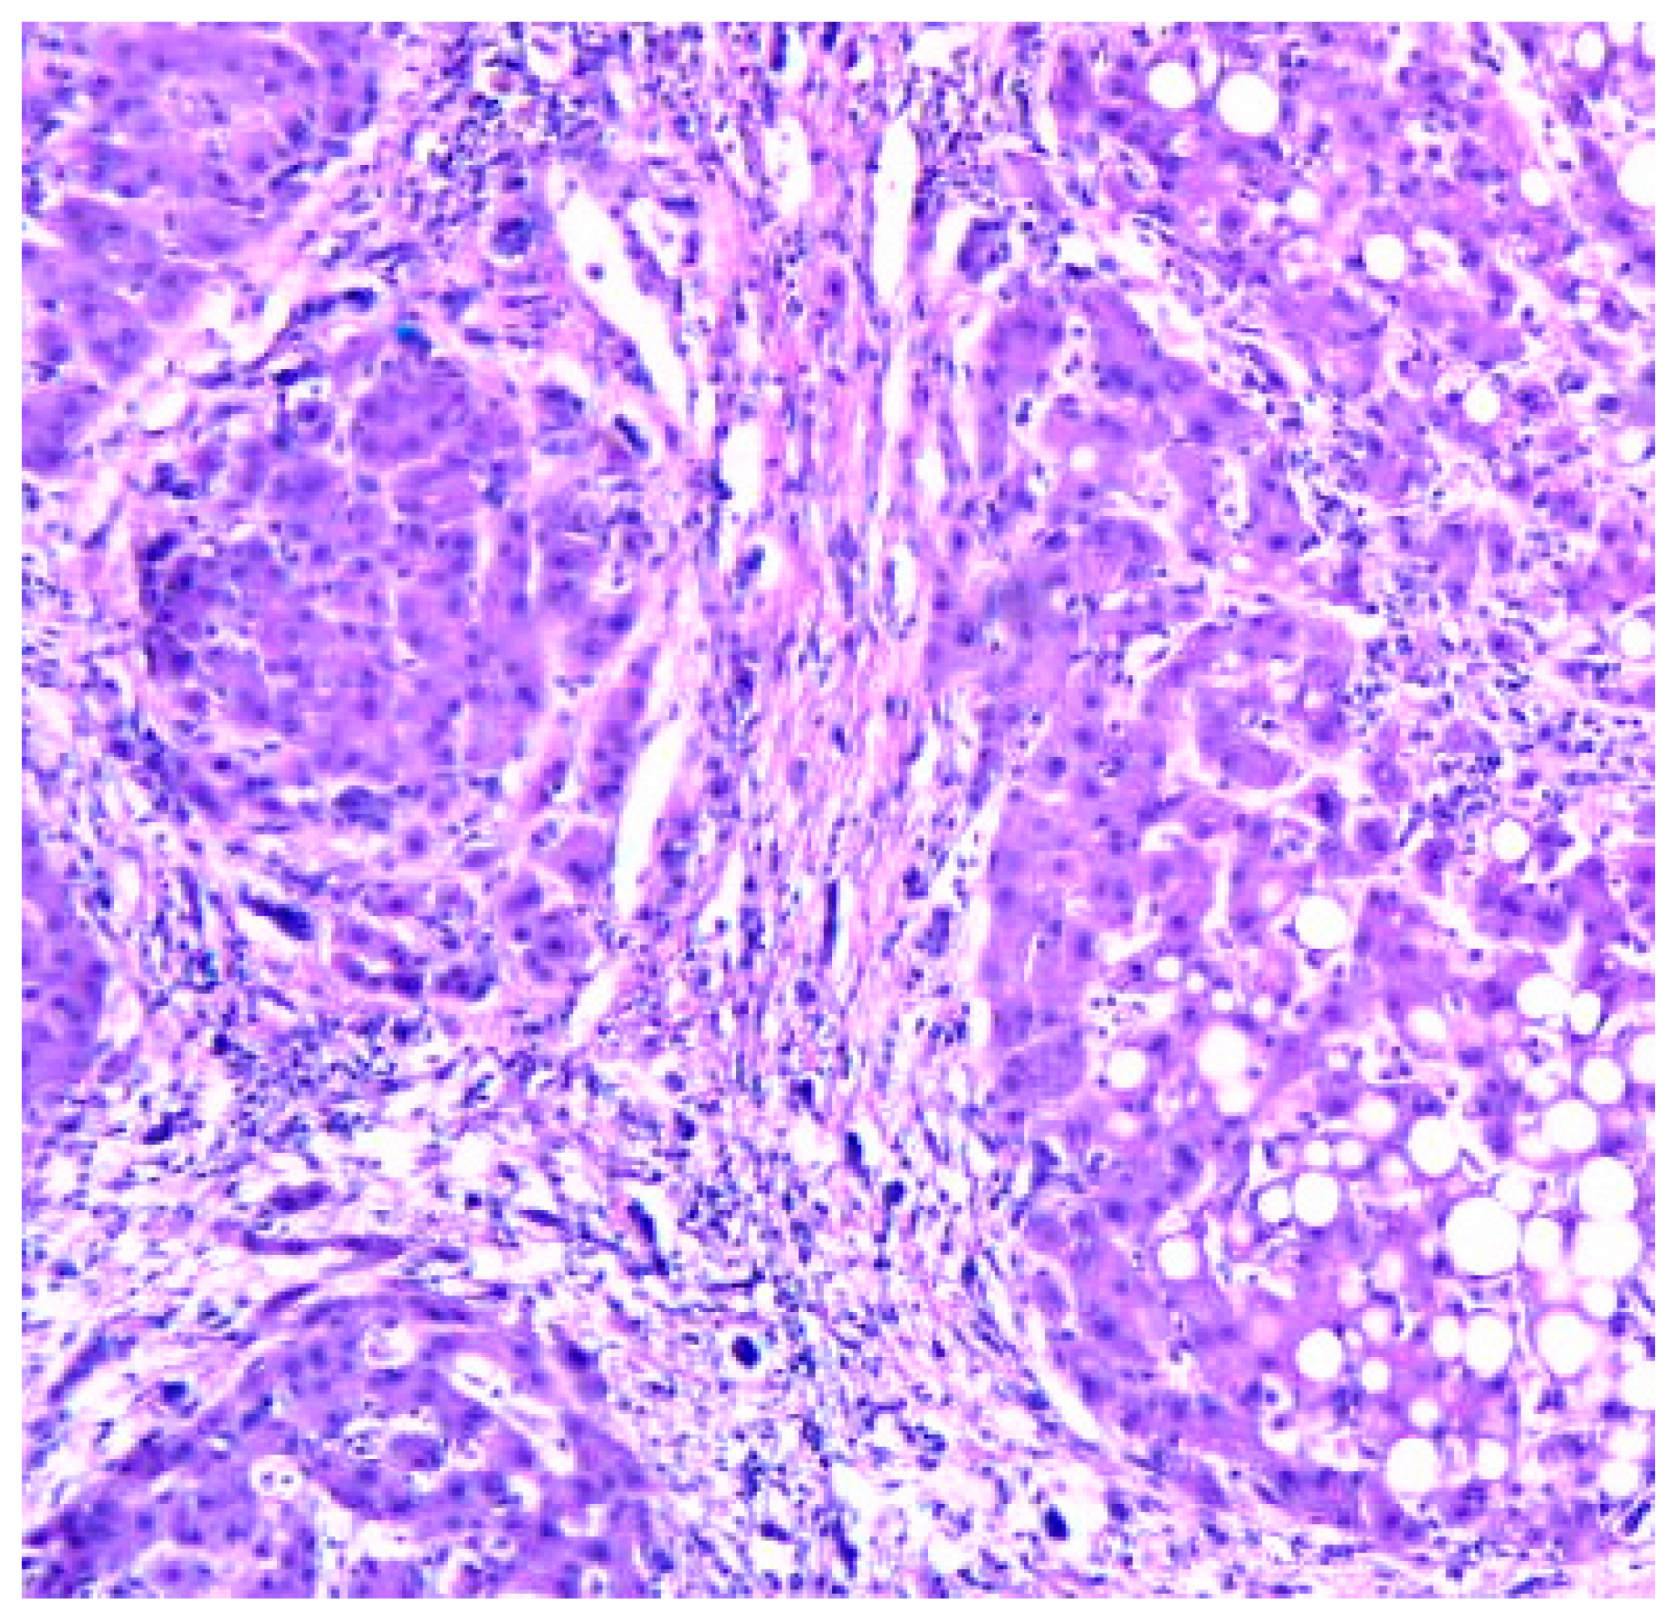

Cirrhosis usually represents with end-stage liver disease. Hepatitis C is the most damaging. Cirrhosis develops after a period of inflammation. The ill liver has parenchyma with fibrotic tissue and regenerative nodules (Figure 4).

Figure 4. Cirrhosis liver x10 H&E stain.